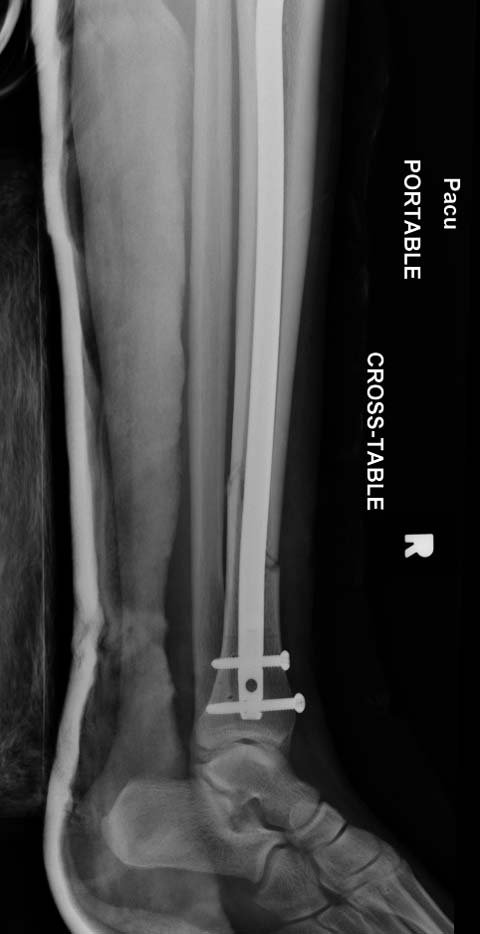

Хотя, по существу, гвоздь действительно короткий, и не смотря на это, заблокирован дистально только одним винтом - не стабильно

1. Гвоздь ОЧЕНЬ коротковат. Нет репозиции большеберецовой, гвоздь в дистальном отломке пошел по задней стенке.

2. Не зафиксирована малоберцовая кость: уровень перелома достаточно низкий, чтобы им пренебрегать. Да и состояние дистального синдесмоза сомнительное.

Ещё не понятно как тут с ротацией, мне кажется это даже более важно , чем варус.

Разбор любого случая кому-то поможет лучше ориентироваться в решении вопросов, потому что в нашей работе встречаются разные связанные и несвязанные с мастерством хирурга ситуации. Возможно, отсутствие полного набора гвоздей повлияло на выбор короткого имплантата, имеется угловая и ротационная деформации. Независимо от локализации, стабильность создается, когда гвоздь проксимально не глубже 1.5 см (облегчает удаление) и дистально доходит до epiphyseal scar.

Мнение о том, что гвоздь сделает репозицию не всегда соответствует истине. Снимки показывают на неудачную попытку исправить направление гвоздя с помощью “поллеров”. Прием возможен только тогда, когда проход риминга в центре канала, иначе толкать гвоздь некуда.